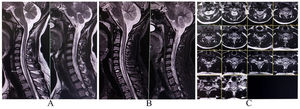

A complete blood cell count, renal and liver function tests, serum electrolytes, blood glucose parameters, creatine phosphokinase levels, vitamins B1, B6, B12, D, E, and copper levels were within normal limits. However, an MRI of the spinal cord revealed a contrast-enhanced T2-hyperintense lesion at C5 to D1 level (Fig. 5A, B, C). Nerve conduction studies showed an acquired sensorimotor axonal polyneuropathy (lower limbs more than upper limbs). Anti-thyroid antibodies (anti-TPO, TRAB, anti-TG) were raised in high titers. Other autoimmune, metabolic, toxic, vasculitic, paraneoplastic, and neuroinfectious etiologies were ruled out with relevant tests. She was put on pulse intravenous methylprednisolone therapy (1 g/day for 5 consecutive days), followed by oral prednisolone in tapering doses for the next 3 months with close monitoring. After a week of intravenous methylprednisolone therapy, motor power normalized, but sensory dysesthesias persisted for another 2 months before abatement. At the sixth month of follow-up, she still required 10 mg/day of prednisolone but was utterly free of any neurological deficit.